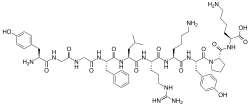

Opioid peptides

Enkephalins

Structures

| Enkephalins | ||||

|---|---|---|---|---|

DAMGO DAMGO |

||||

Structures

| Other or unknown opioid peptides | ||||

|---|---|---|---|---|

Endomorphin-1 Endomorphin-1 Endomorphin-2 Endomorphin-2 |